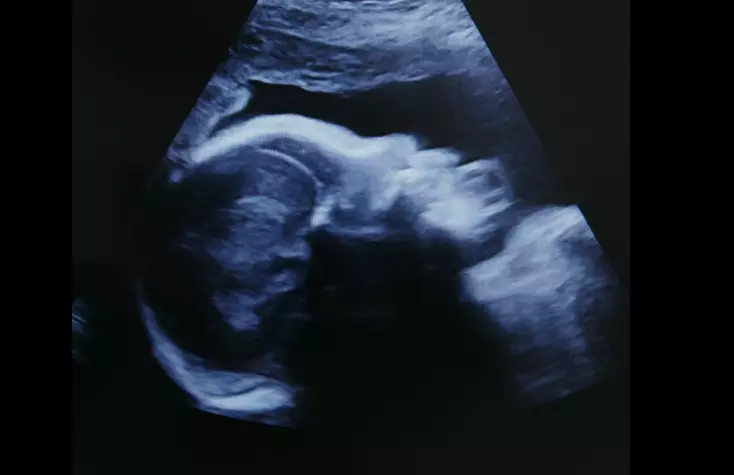

For starters, test results are not always accurate. Prenatal testing is often initiated in the first trimester of pregnancy using tests that are known to have very high false positive rates, as has been noted by peer-reviewed research, the Food and Drug Administration, and even the New York Times. Unfortunately, parents often are not aware of these test inaccuracies, resulting in needless trauma and, at times, the tragic abortion of healthy babies.

When a prenatal diagnosis is confirmed, like any parent upon hearing their child is sick, parents want to learn what care and treatment options are available. The good news is that medicine is advancing rapidly in the care of these children both before and after birth, with specialized treatments becoming more widely available. It is sadly ironic that the Biden administration is promoting abortion for babies with prenatally diagnosed conditions even as children’s hospitals are running TV and billboard ads featuring life-saving fetal surgeries for some of these same children.

While not all conditions can be cured, medical advances can improve the lives of many children. In the case of Trisomy 18, physicians who care for and treat these children emphasize that each child is unique with specific medical needs, and with appropriate medical care, some of these children may live for decades.